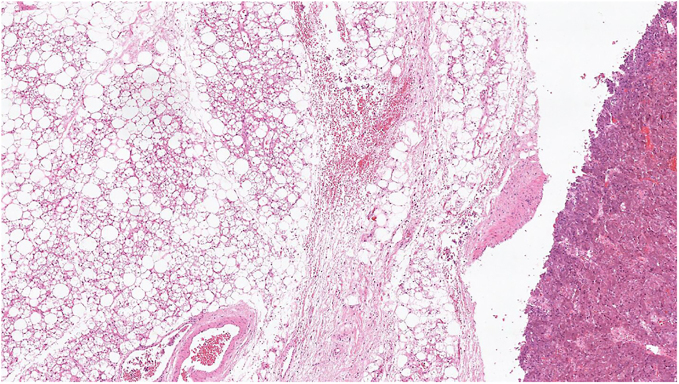

Brown adipose tissue (BAT) activity, identifiable through fluorodeoxyglucose positron emission tomography (FDG-PET), has gained interest due to its potential link with metabolic disorders and tumour pathophysiology. This study aims to explore the activation of BAT in patients with phaeochromocytoma/paraganglioma (PPGL) and its clinical relevance. This retrospective observational study, conducted in a large academic centre in London, reviewed FDG-PET images of 62 confirmed PPGL patients, collected between 2013 and 2021. We assessed patient demographics, biochemistry, radiological features, mutational status and outcomes, focussing on activated BAT detection. Of the 62 patients, 13% demonstrated active brown adipose tissue (aBAT) on FDG-PET imaging. Histopathological confirmation of BAT from one patient was used to validate BAT activation observed during imaging. Multivariate analysis indicated that elevated plasma normetanephrine concentrations were directly proportional to aBAT presence, suggesting their strong association with BAT activation. Despite identifying aBAT, no significant differences were found in BMI, sex, age or mutational status between aBAT-positive and aBAT-negative groups. Kaplan-Meier survival plots assessing overall and progression-free survival did not reach statistical significance. This study underscores the complex interaction between catecholamine excess and BAT activation in patients with PPGLs. The findings suggest that aBAT activity might be an indicator of severe catecholamine excess (especially normetanephrine), potentially influencing patient outcomes. Our study adds to the limited pool of knowledge and offers novel insights into BAT activation in patients with PPGLs, highlighting its potential link with metabolic derangements and patient outcomes.